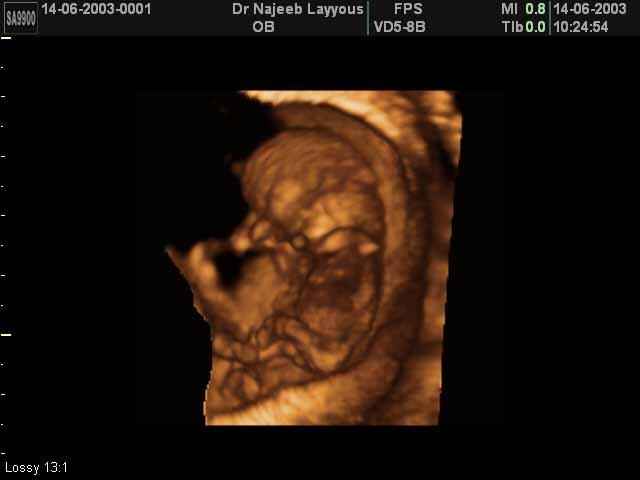

3D First Trimester Ultrasound Scan Photos